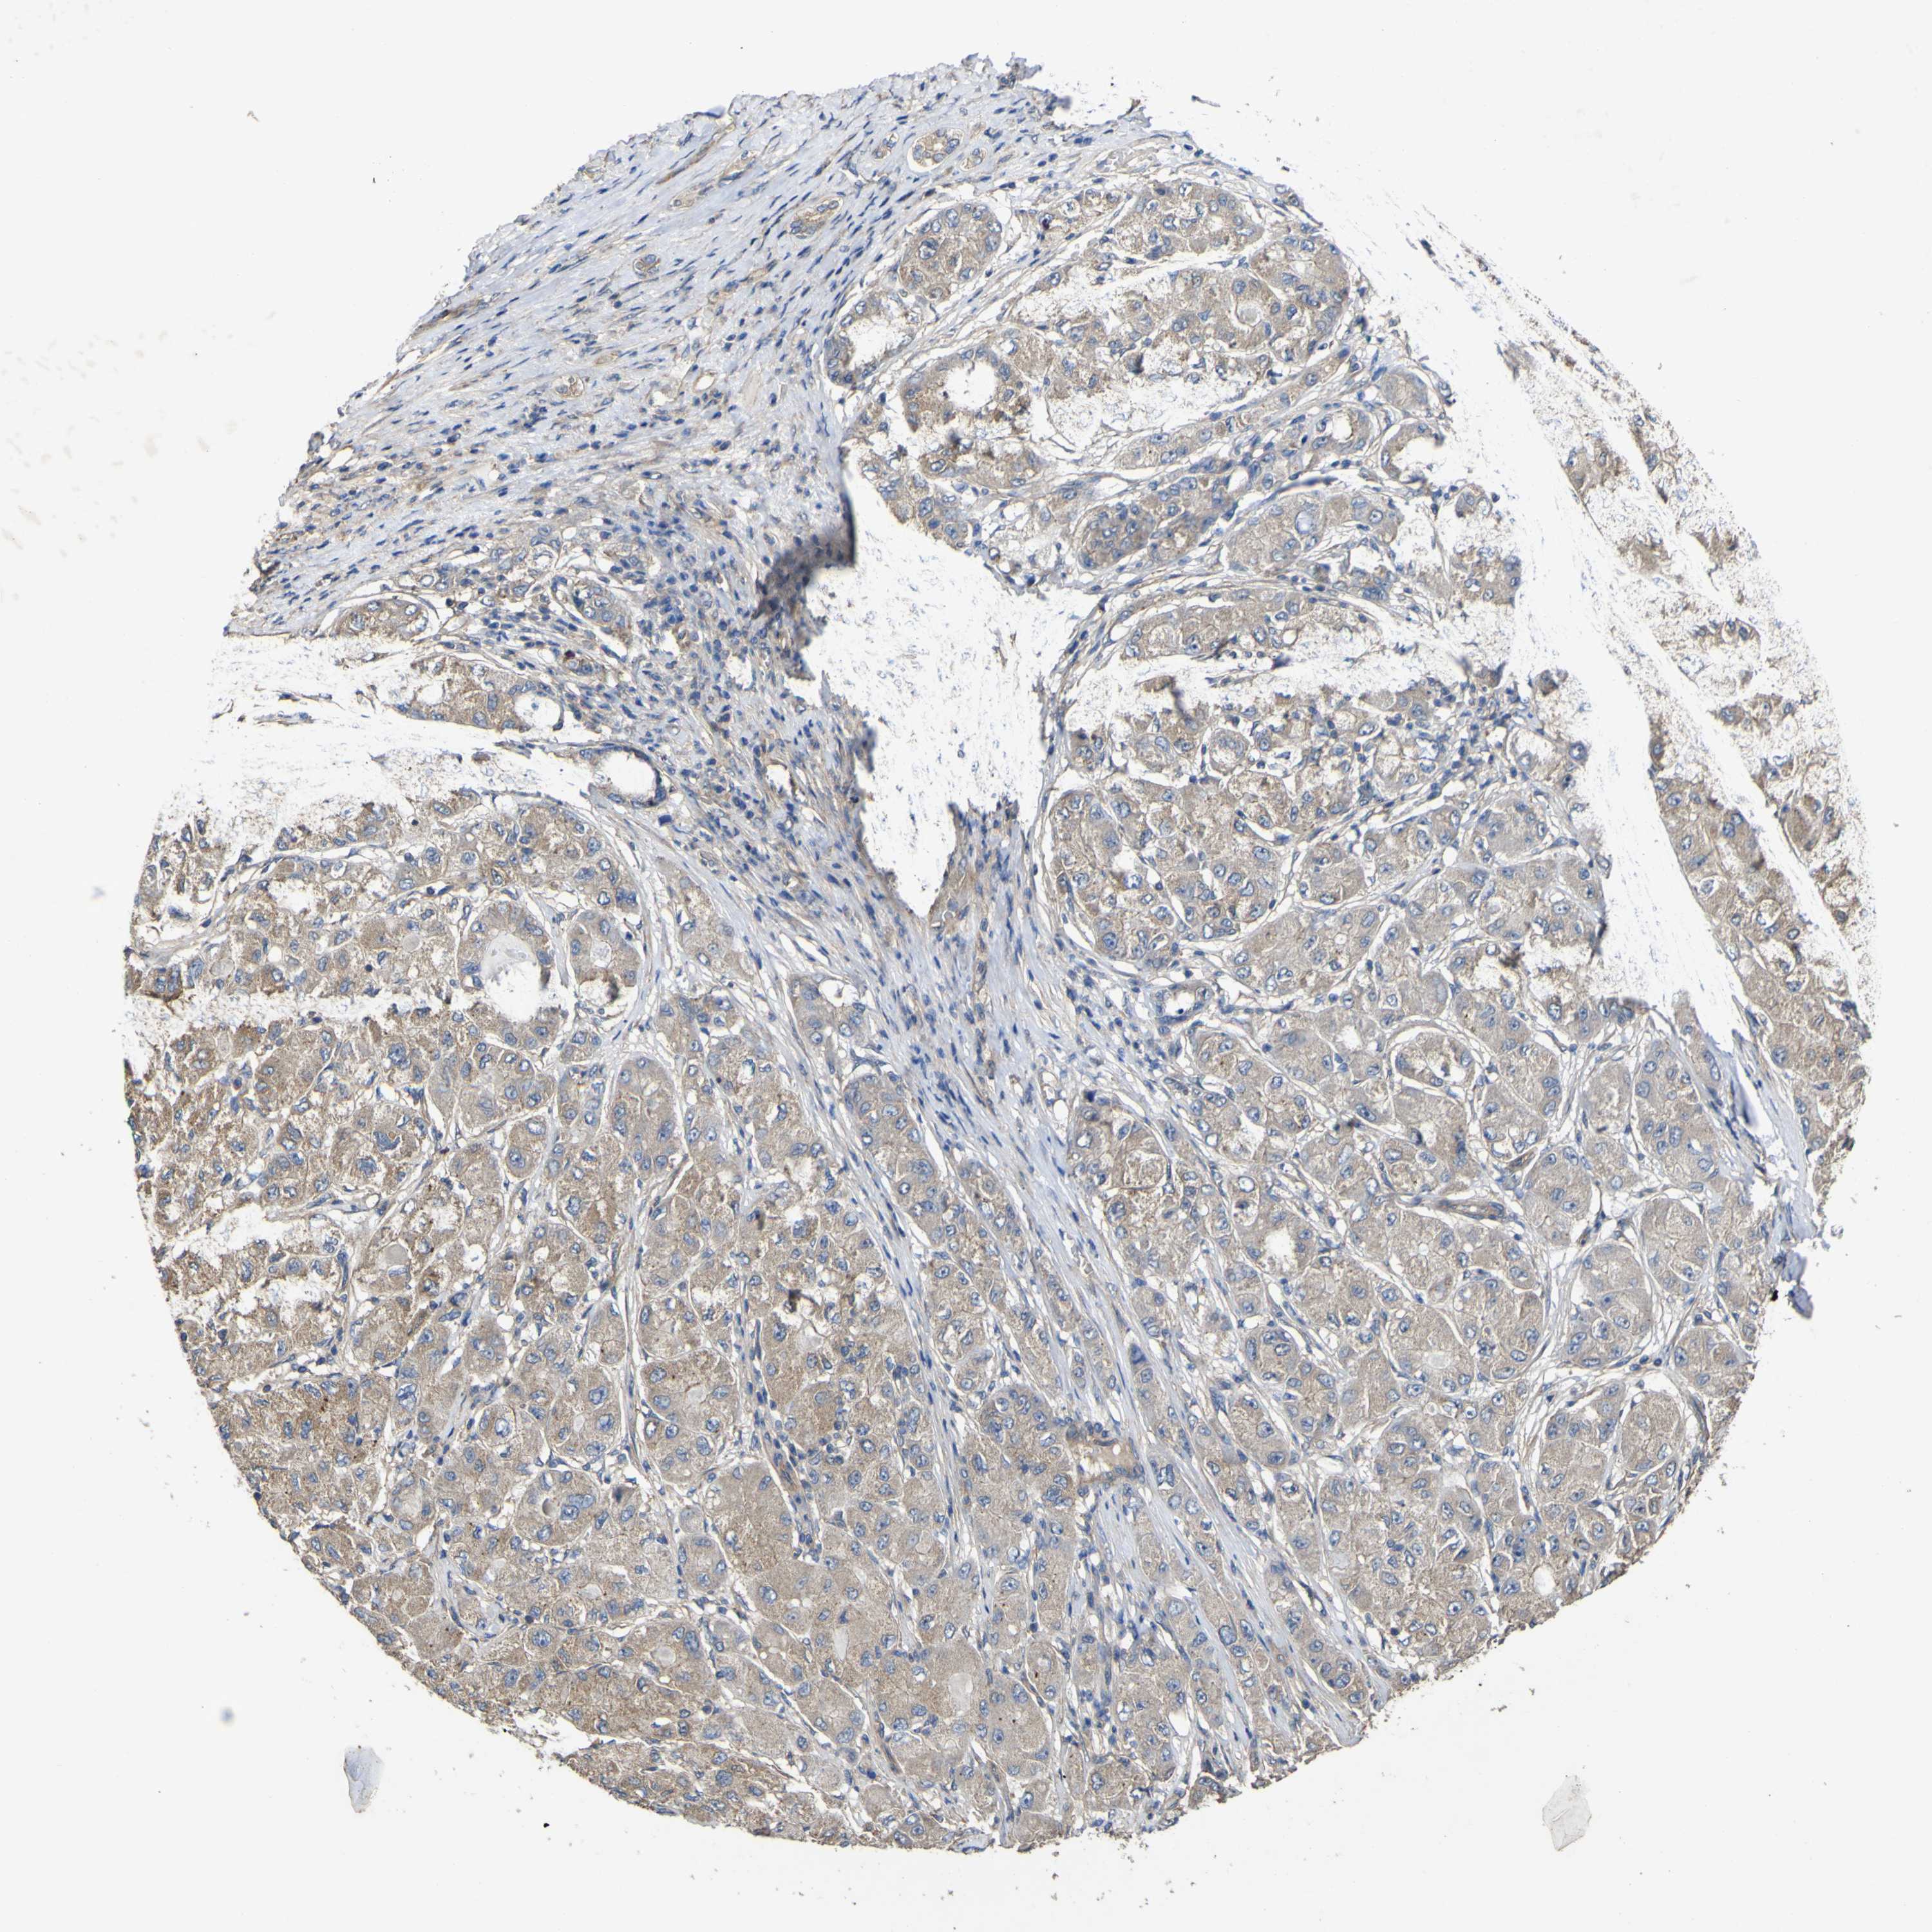

LIVER CANCER - Protein expressioni

A mouse-over function shows sample information and annotation data. Click on an image to view it in a full screen mode. Samples can be filtered based on level of antibody staining by selecting one or several of the following categories: high, medium, low and not detected. The assay and annotation is described here.

Note that samples used for immunohistochemistry by the Human Protein Atlas do not correspond to samples in the TCGA dataset.

Antibody stainingi

Antibody staining in the annotated cell types in the current human tissue is reported as not detected, low, medium, or high, based on conventional immunohistochemistry profiling in selected tissues. This score is based on the combination of the staining intensity and fraction of stained cells.

Each image is clickable and will lead to virtual microscopy that enables deeper exploration of all samples and also displays staining intensity scores, fraction scores and subcellular localization as well as patient and tissue information for each sample.

Antibody HPA012948

Staining

High

Medium

Low

Not detected

Intensity

Strong

Moderate

Weak

Negative

Quantity

>75%

75%-25%

<25%

None

Location

Nuclear

Cytoplasmic/membranous

Cytoplasmic/membranous,nuclear

Cholangiocarcinoma

Carcinoma, Hepatocellular, NOS